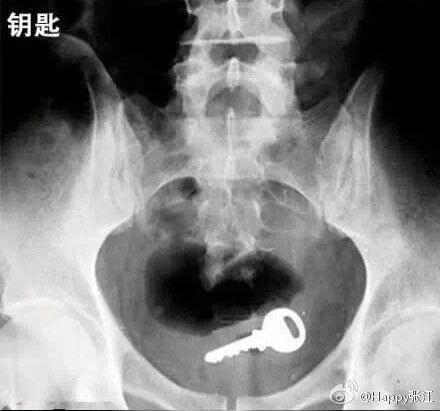

据说这是医生们盘点的肛门塞入东西的奇葩之最,毁三观啊